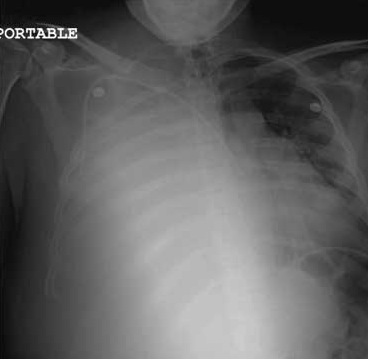

A chest radiograph revealed complete opacification of the right lobe and partial opacification with infiltrate of the left lung, suggestive of acute pneumonia. Metastasis of the testicular cancer to the lungs was suspected. The patient was transferred to a tertiary care center for further evaluation and treatment by an oncologist. Further testing, including thoracentesis, confirmed the metastasis.